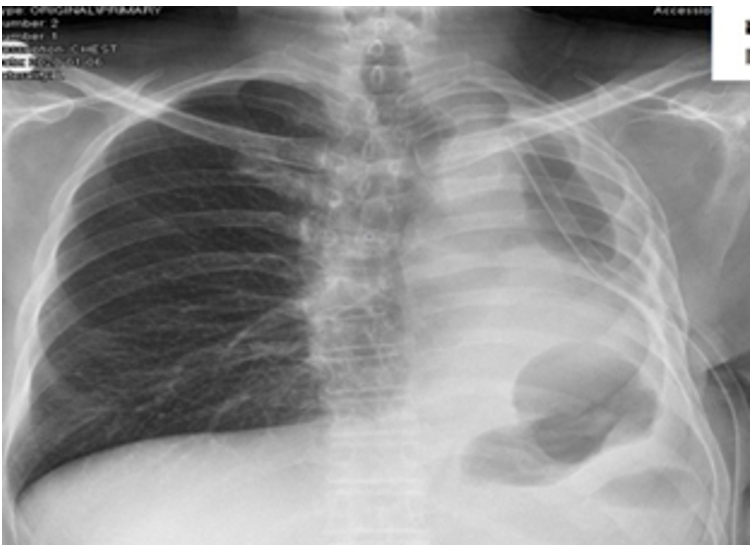

The most common symptoms in both groups were fever, cough, chest pain, and shortness of breath. All patients were diagnosed by chest X-ray and mostly by computed tomography (CT) of the thorax.

All patients had air trapping and, fluids could not be obtained by thoracentesis or with catheter/tube thoracostomy (Figure 1, 2). Consequently, all patients underwent posterolateral thoracotomy.

Figure 1. Chest X-ray of a patient with empyema